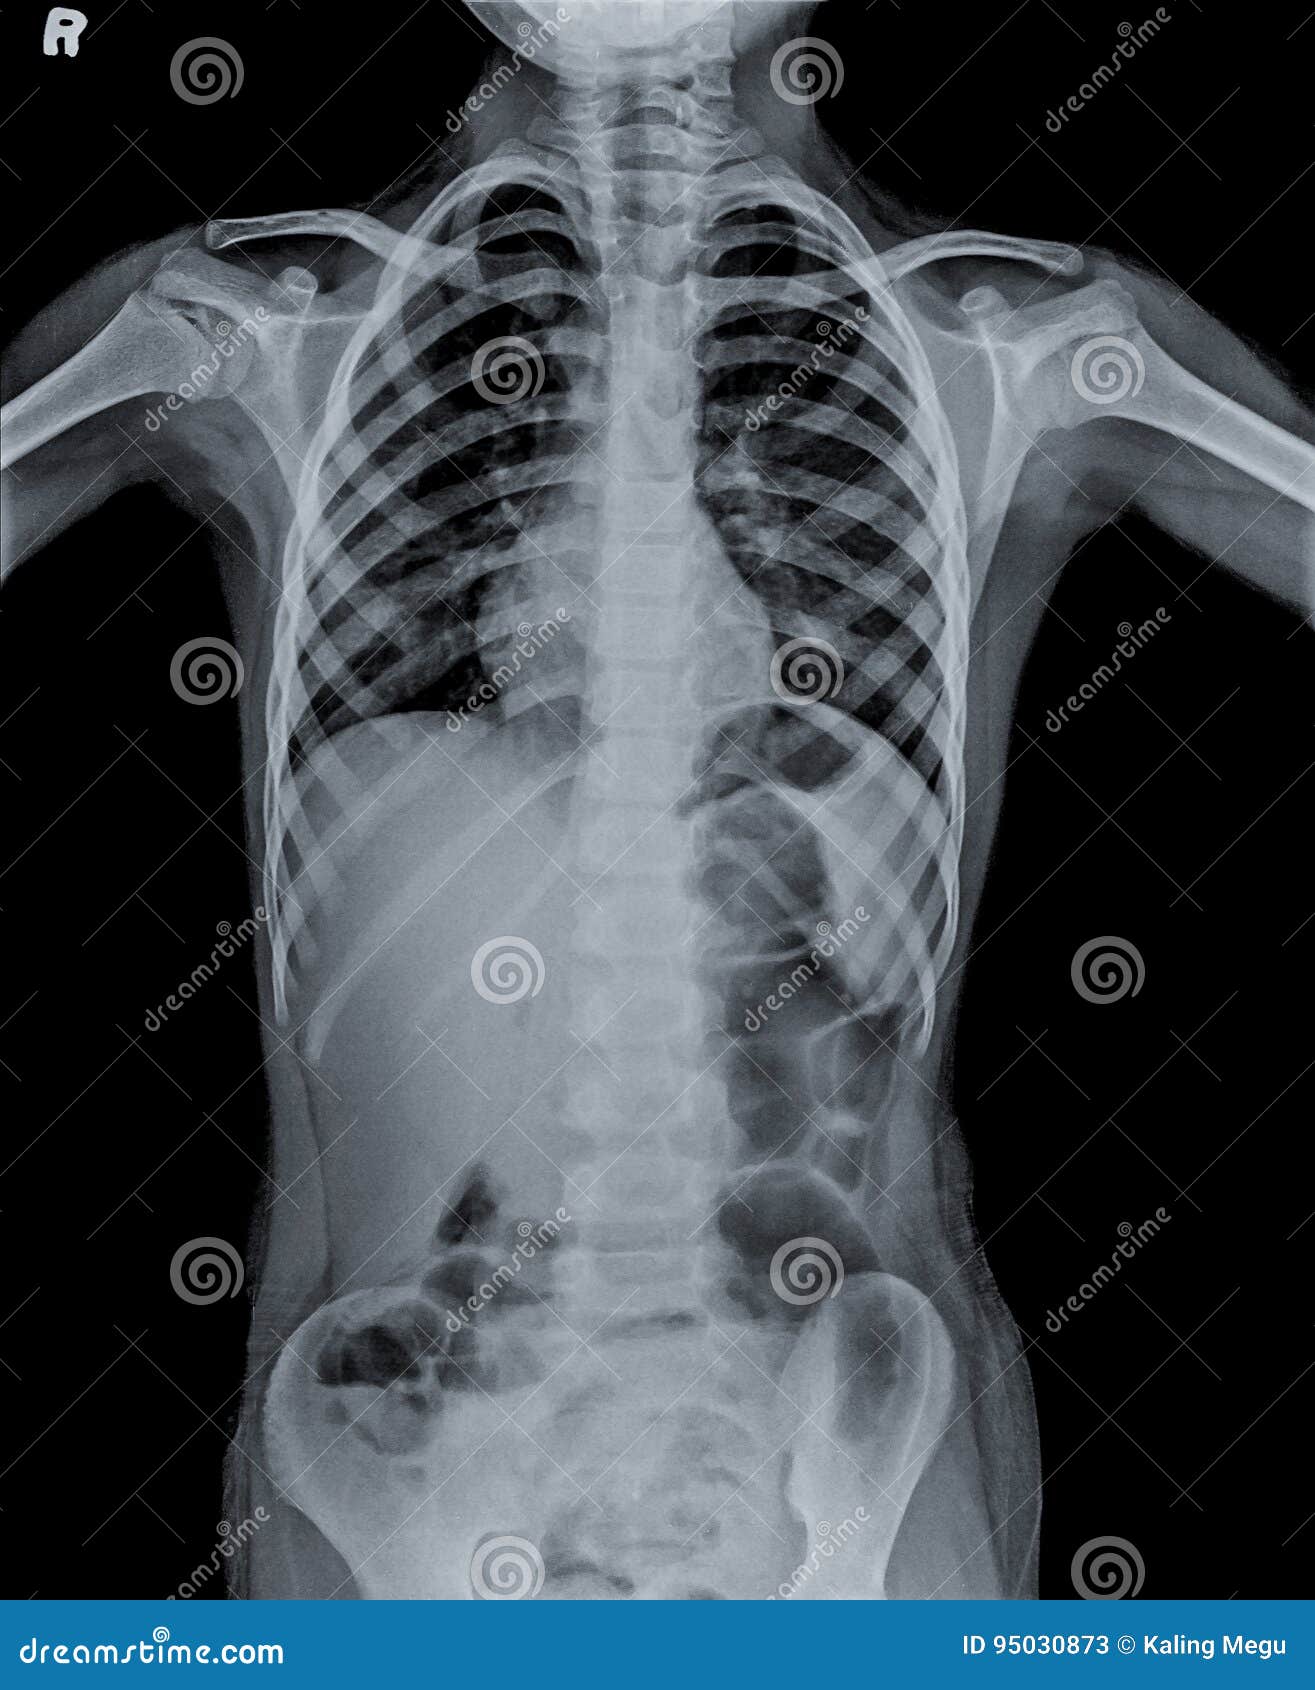

Whole-body X-ray of the fetus at birth. | Download Scientific Diagram

Whole body X-ray of the infant. | Download Scientific Diagram

Cuerpo Entero De La Radiografía De La Película Del Niño Imagen de …

Pediatric full body x-ray phantom of a child with fractures

Pediatric full body x-ray phantom of a child with fractures

X-Rays and Unshielded Infants Raise Alarms – The New York Times

Pediatric full body x-ray phantom of a child with fractures

Film X-ray Whole Body of Child ( Medical , Science and Healthcare …